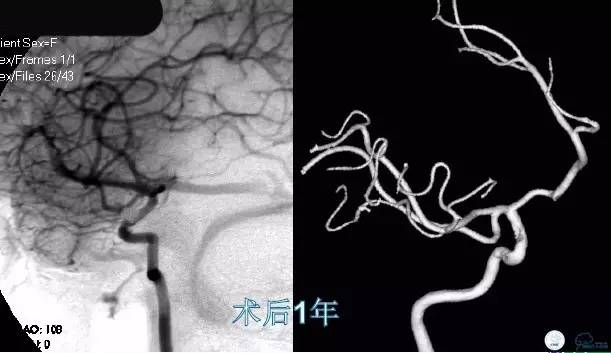

Case2 左ICA床突旁动脉瘤术后稳定

影像随访:术后6个月第一次复查造影,如果随访结果稳定,1~2年再复查一次。